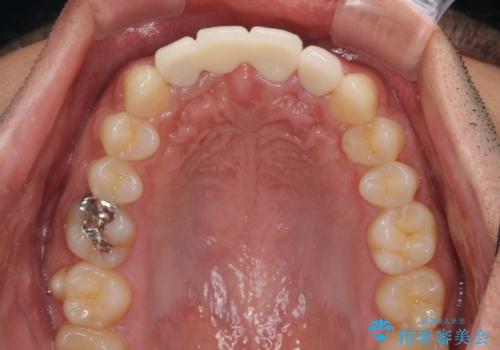

転んでぶつけて抜歯 前歯のオールセラミックブリッジ

- 酒席の後に転倒して前歯を損傷し、応急処置のみを受けてきたとのことで来院された患者様です。

損傷がひどく、前歯4本と広範囲であったため、症状やレントゲン写真、検査結果が一致せず、定期的に経過を見ながら診断していくこととしました。